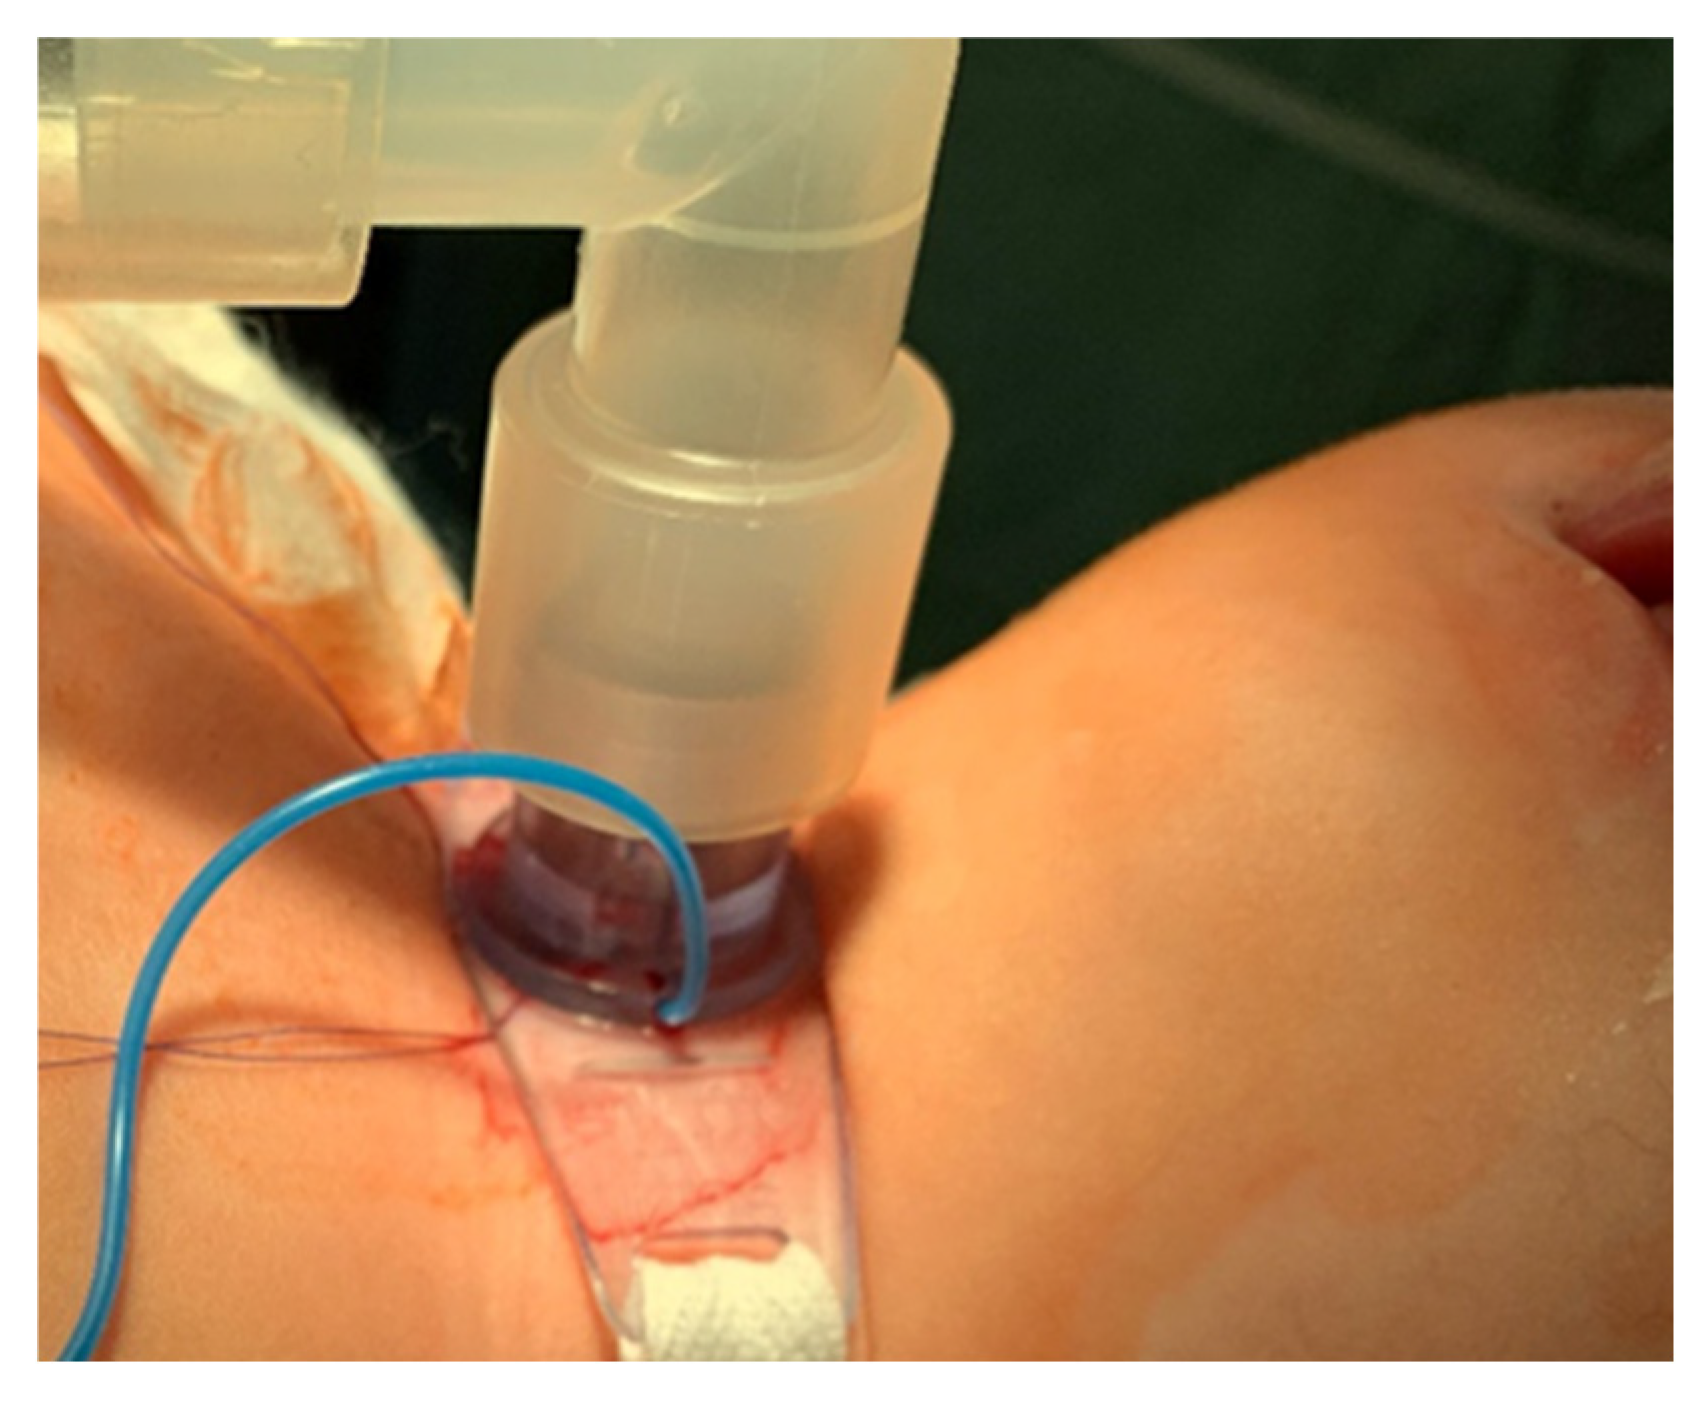

- The cannula is connected to the ventilator, and its cuff is inflated (Figure 7).

- After confirming the correct position of the cannula, the hook and retractor are removed.